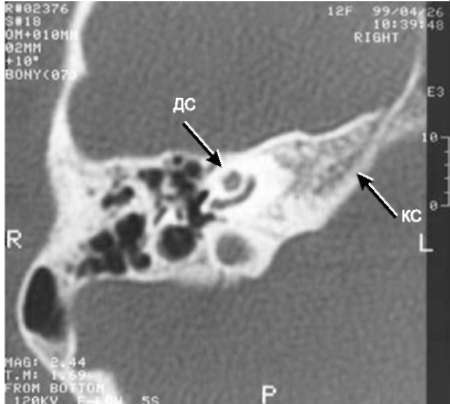

pic 0140

Рис.11-6. КТ, коронарная проекция. Третья часть канала лицевого нерва дистопирована кпереди (ДС) и располагается на уровне ямки окна преддверия (КС).

Подробные данные КТ височной кости при оценке структур наружного, среднего и внутреннего уха у детей с врождёнными атрезиями наружного слухового прохода необходимы для оценки технической возможности формирования наружного слухового прохода, перспективности улучшения слуха, оценки степени риска предстоящей операции. Ниже приведены некоторые типичные аномалии (рис. 11-4-11-8).